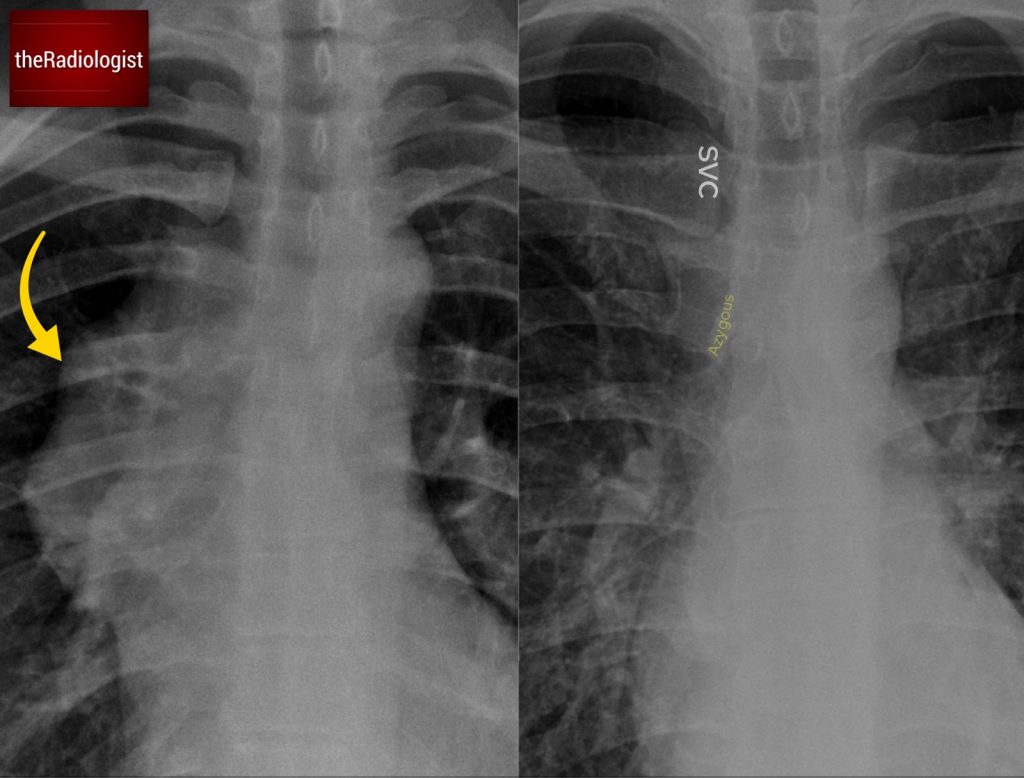

To get oriented, let’s start with a comparison and compare our case with a normal X-Ray.

Normal Anatomy

In a normal X-ray, we should be able to see the faint outline of the brachiocephalic veins draining into the superior vena cava (SVC) on the right side of the mediastinum.

You can also see a small contour representing the azygos vein just above the right main bronchus.

Our Case

In this case, those normal contours are missing. Instead, we see an abnormal contour along the right side of the mediastinum.

Compare the normal anatomy (right) with our case (left). In normal circumstances we should be able to see a faint opacity reflecting the SVC and brachiocephalic veins as well as an azygos contour. In our case these are more difficult to spot with an abnormal contour to the right side of the mediastinum.

Look through the mass and you will see the right hilar vessels: if you can see the vessels through a hilar mass (yellow arrow) this is called the hilum overlay sign and points you away from a middle mediastinal lesion.